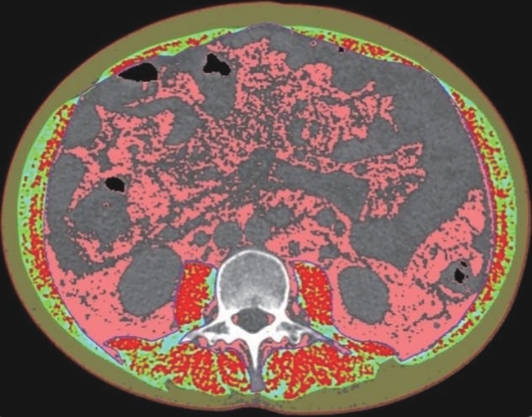

Value of internal stratification analysis of abdominal wall muscles in predicting complications after orthotopic liver transplantation

Xin SHI, Chongxiao LIANG, Bei ZHANG, Jiping WANG

2025, 41(2): 314-321. DOI: 10.12449/JCH250218

Abstract(741) HTML (353) PDF (3265KB)(54)

Abstract:

Objective  To divide the muscle into different subzones according to different density ranges using the stratified analysis on the basis of myosteatosis, and to investigate the effect of muscle density changes on complications (Clavien-Dindo grade ≥Ⅲ) after orthotopic liver transplantation (OLT).  Methods  A retrospective analysis was performed for the medical records of 145 patients who underwent OLT in The First Hospital of Jilin University from May 2013 to September 2020, and with the plain CT scan images of the largest level of lumbar 3 vertebrae of each patient as the original data, Neusoft Fatanalysis software was used to measure related muscle parameters. The independent-samples t test was used for comparison of normally distributed continuous data between two groups, and the Mann-Whitney U test was used for comparison of non-normally distributed continuous data between two groups. The chi-square test or Fisher test was for comparison of categorical data between two groups. RIAS software was used to extract clinical features and perform analysis and modeling, and three machine learning models of logistic regression (LR), support vector machine (SVM), and random forest (RFC) were constructed. The receiver operating characteristic (ROC) curve, the calibration curve, and the decision curve were plotted for each model to calculate the area under the ROC curve (AUC), sensitivity, specificity, precision, F1 score, and accuracy.  Results  The three machine learning models of LR-C, SVM-C, and RFC-C were established based on the 7 clinical features before muscle stratification analysis, among which the RFC-C model had an AUC of 0.803, a sensitivity of 0.588, and a specificity of 0.778 in the test set. Among the models of LR-CS, SVM-CS, and RFC-CS established based on the 16 clinical features after muscle stratification analysis, the LR-CS and SVM-CS models had an AUC of 0.852 in the test set, with a sensitivity of 0.765 and 0.706, respectively, and a specificity of 0.889 and 0.926, respectively. Comparison of the AUC, sensitivity, specificity, precision, F1 score, and accuracy of each model in the test set before and after muscle stratification analysis showed that there were improvements in the parameters of the predictive model after muscle stratification analysis. Comparison of the decision curves and calibration curves of each predictive model showed that the LR-CS and SVM-CS models had good efficacy in predicting postoperative complications (Clavien-Dindo grade≥Ⅲ) in OLT patients.  Conclusion  On the basis of myosteatosis, the division of the muscle into different subzones according to different densities using the stratified analysis has a certain value in predicting postoperative complications in patients with OLT.